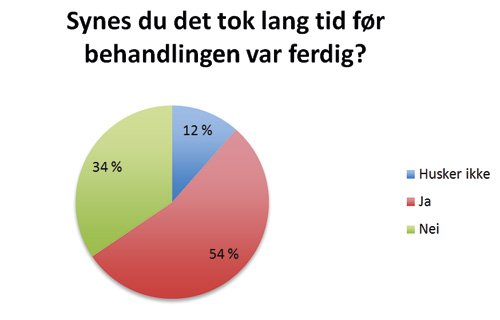

Formålet med denne studien var å vurdere resultater og komplikasjoner etter lukket fremføring av palatinalt retinerte hjørnetenner, samt å se på pasientenes subjektive opplevelse av behandlingen. Studien viser at 90 % av pasientene som responderte på tilsendt spørreskjema var fornøyde med resultatet. At de var fornøyde så ut til å være uavhengig om de opplevde peroperative- eller postoperative smerter. Heller ikke lang behandlingstid så ut til å redusere andelen fornøyde pasienter. Informasjon om endelig behandlingsresultat ble innhentet fra henvisende kjeveortopeder for 54 av pasientene. 52 av disse pasientene oppnådde vellykket fremføring av retinert tann. I de to tilfellene der resultatet ikke ble vellykket, ble tannen fjernet. Studien har i tillegg vist at frekvensen av komplikasjoner er lav etter behandling.

Synes du det tok lang tid før behandlingen var ferdig?

En oversikt over antall forespurte og antall responderende pasienter sees i Tabell 1. Totalt 85 pasienter som samtykket til å delta i studien kunne identifiseres. For disse var det aktuelt å innhente journalopplysninger fra fakultetet og henvisende kjeveortoped. Hvordan pasientene opplevde operasjonen og behandlingen etterpå er presentert i Figur 2 - 6.

Figur 6. Synes du det tok lang tid før behandlingen var ferdig?

Den subjektive opplevelsen til pasientene etter behandling av palatinalt retinerte hjørnetenner ved lukket fremføring ble vurdert ut fra svarene fra spørreskjemaet som ble sendt til den enkelte pasient. Vi har ikke funnet noen tidligere studier hvor spørreskjema er benyttet i evaluering av denne type behandling. 90 % av pasientene var fornøyde med resultatet etter behandling. Vår studie viser også at pasientene stort sett er fornøyd uavhengig om pasienten har opplevd smerte under eller etter operasjonen. 20 % av pasientene som oppga at det var svært smertefullt under operasjonen oppga at de ikke var fornøyd med resultatet mot kun 4 % av dem som oppga noe smerter under operasjon. Blant de pasientene som synes at hele prosessen med å få dratt frem hjørnetann var veldig ubehagelig, er det overvekt av pasienter som er fornøyd med resultatet. At 39 av 47 pasientene var fornøyde selv om de svarte at de synes det tok lang tid, gjør at man kan anta at lang behandlingsperiode heller ikke er avgjørende for om pasienten blir fornøyd.

Ved økt fokus på smertekontroll, vil muligens færre pasienter føle at opplevelsen av hele prosessen var veldig ubehagelig, noe som hele 22 % svarte. Her må man ta i betraktning at «opplevelsen av hele prosessen» gjelder både den kirurgiske og kjeveortopediske delen av behandlingen. Vi ser i denne studien at det gjennomsnittlig tar 2 år fra frilegging av tann til debonding. Det at over halvparten av pasientene synes at behandlingen tok lang tid, er derfor ikke et overraskende resultat. Fremføring av en palatinalt retinert hjørnetann er en tidkrevende behandling, og man kan ikke risikere negativt utfall av behandlingen bare for å oppnå kortere behandlingsperiode for pasienten. Om pasientene synes behandlingen tok lenger tid enn det de i utgangspunktet forventet, er usikkert. Det er viktig at pasienten er innforstått med den lange behandlingstiden de har i vente. Muligens er ytterligere informasjon til pasient og foresatte angående den forventede behandlingstiden, nødvendig.

Studien viser at pasienter som har gjennomgått behandling av palatinalt retinerte hjørnetenner ved lukket fremføring med feste av sleper er fornøyde med resultatet. At de er fornøyd med resultatet er stort sett uavhengig av om de har opplevd smerter under eller etter operasjon. I tillegg ser det ut til at de fleste pasientene som synes behandlingsperioden er lang, likevel er fornøyde med resultatet. Også blant pasientene som syntes hele prosessen med å få fremført en tann var ubehagelig er en overvekt av pasientene fornøyde.